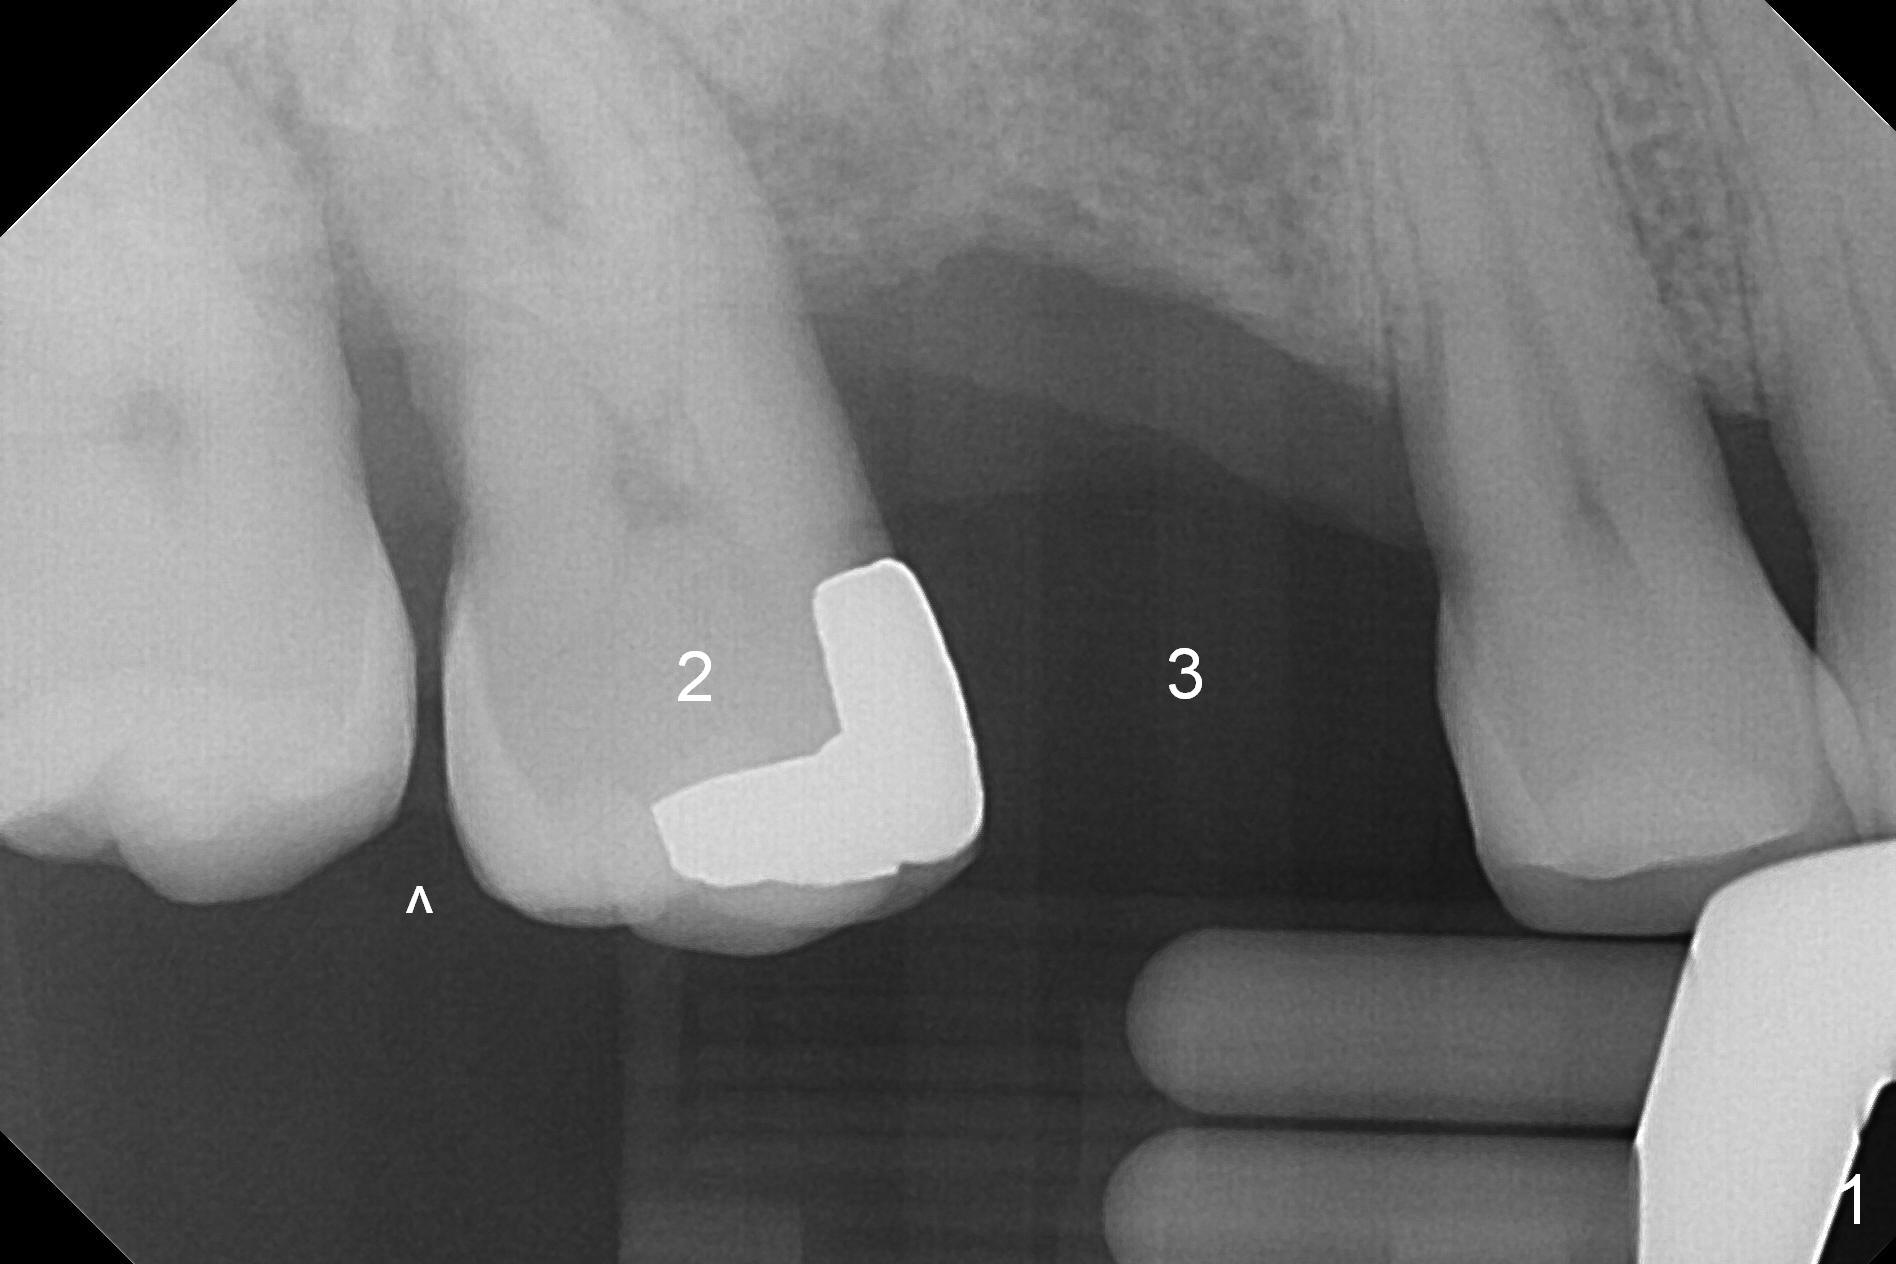

A 53-year-old man wants treatment so that the tooth #2 will not have the fate of the tooth #3. It appears that etiology includes periodontitis and occlusal trauma (Fig.1, 2). The tooth #2 has shifted mesially (Fig.1 ^). The initial drill of DIO Sinus Lift Master Kit will be used for 6 mm (Fig.2), followed by round burs for 7 mm or more. Place PRF and allograft (Metronidazole) before implant placement.

After implant osteointegration, fabricate a provisional and place a separator between #2 and 3. A few days later, add acrylic to the distal surface of the provisional and place a separator. The procedure will repeat until the distal diastema of the tooth #2 closes. Make necessary occlusal adjustment for #2 so that it does not get occlusal trauma.